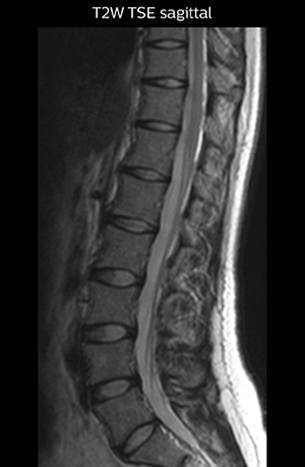

The key concept in MR neurography, Dr. Yabuki stresses, is the ability to directly visualize spinal nerves, versus inferring the presence of pathology indirectly. “Before NerveVIEW, we estimated compression of the nerve by looking for the presence or absence of fat signal on other MR images,” he says.

“For example, in sagittal images, when the presence of fat is observed in the intervertebral foramen, it suggests that there is a margin around the nerve. Similarly, the absence of fat indicates that the nerve is being compressed. So, we used to deduce nerve compression indirectly. With NerveVIEW, however, we can observe the condition of the nerves directly, regardless of the presence or absence of fat. We always prefer such direct observation of anatomy over having to make an inference about it.”

Good spatial resolution is required

“For both brachial and lumbar plexus, we are currently using a 230 mm FOV and voxels of about 1 x 1 x 2 mm acquired (1 x 1 x 1 mm reconstructed). This provides us a good representation of the nerves, even though this FOV is relatively small. Regarding the inplane resolution, we hope to be able to bring that down to 0.7 mm, similar to our typical 2D multislice T2W images,” says Tanji.

“Recently, the two surgical methods extreme and oblique lateral interbody fusion (XLIF and OLIF) have become mainstream for minimally invasive treatment of lumbar spinal canal stenosis and intervertebral foramen stenosis. With these surgical techniques, the spine is approached from the flank, and prior knowledge of the exact anatomy of the lumbosacral plexus would be extremely helpful. To that end, high slice resolution (less than 1 mm acquisition) that enables sharper sagittal MPR images will be needed.”